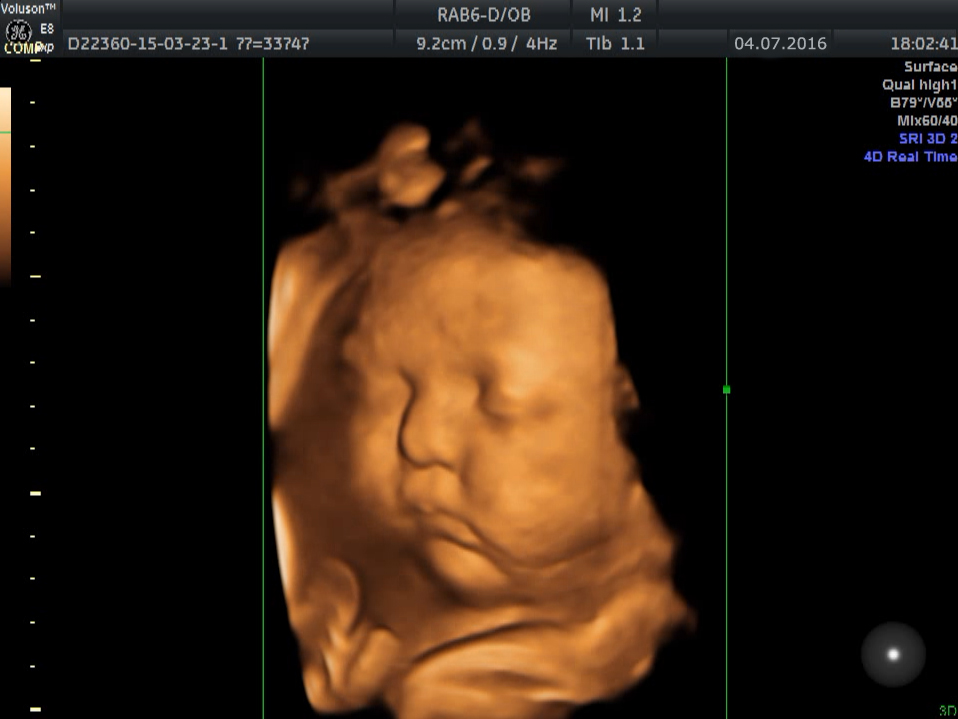

Клиника «АБИА» приглашает будущих мам пройти это безболезненное и очень важное обследование, позволяющее вовремя выявить возможные отклонения в здоровье плода. Что может быть важнее знания, что с малышом всё хорошо? Также мы делаем фото плода и записываем видео УЗИ на электронный носитель – это очень приятная память о волнительном периоде беременности.

| Скрининговое УЗИ плода + 3D/4D УЗИ (один плод) | 5500 |